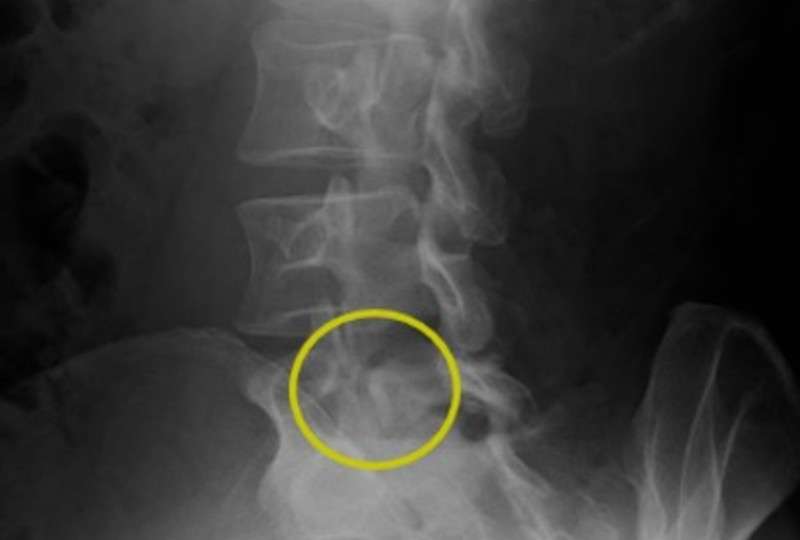

画像所見

画像上の黄色の丸の中に骨の亀裂が確認できます。

また腰の反りが強い印象も見受けられます。